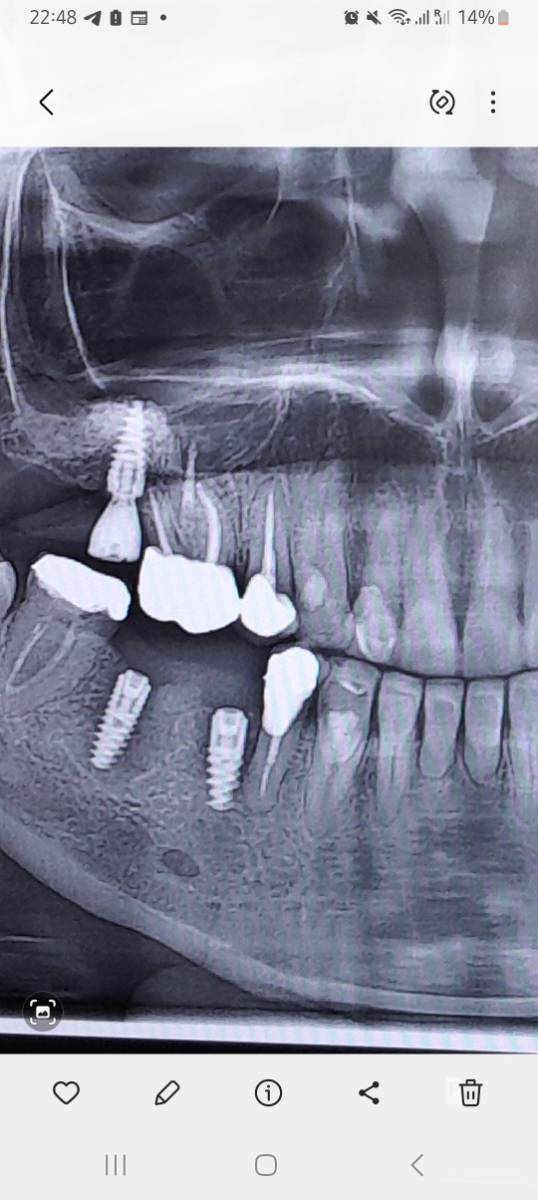

Irina xyz Опубликовано 17 ноября, 2025 Поделиться Опубликовано 17 ноября, 2025 (изменено) 26 окт поставили имплант на 45 29 окт заболел 44 Решили "попробовать" авось пройдет (врач решил) Попробовали Острая боль прошла, чувствительность 44го сохранилась 16 ноября распухла десна Снимок сделан сегодня Здесь снимок от 26го окт Решили еще "попробовать" Вскрыли, поставили теперь формирователь (?).. а вдруг поможет... Есть большие сомнения Отсюда вопрос Можт лучше просто удалить имплант и потом как врсстановится переделать? ... потому что имплант очевидно слишком близко к 44 му зубу и там меньше миллиметра намвыходе между фармирователем и 44м . Изменено 17 ноября, 2025 пользователем Irina xyz . Ссылка на комментарий

Irina xyz Опубликовано 17 ноября, 2025 Автор Поделиться Опубликовано 17 ноября, 2025 То есть то что так близко к 44му - это нормально? Его бы на 0 5-1 мм бы подвинуть от 44 особенно в нижней части .. есть ощущение что имплант на грани кости и тканей вокруг зуба.. отого и 44 реагирует.. Нет? Ссылка на комментарий

сирена Опубликовано 18 ноября, 2025 Поделиться Опубликовано 18 ноября, 2025 44 реагирует от воспаления(периимплантита), имплант надо удалить и месяца через 3 переставить. Задержите протезирование, но зато с хорошим прогнозом. Там нет экстремальной близости к зубу, просто так получилось, что именно этот воспалился. Бывает такое. 1 1 Ссылка на комментарий

Irouil Опубликовано 20 ноября, 2025 Поделиться Опубликовано 20 ноября, 2025 Проще всего имплант удалить, сразу можно будет и проверить причину боли - он или зуб. Если не поможет удаление импланта - надо бф перелечить/удалить зуб Но очевидных показаний к удалению я не вижу, есть деминерализация костной ткани вокруг, может быть признаком "отторжения", а может и пройти (и установка формирователя выглядит тут разумной мерой в попытке спасения импланта) Я бы удалил, но часть решения лежит и на Ваших плечах Ссылка на комментарий